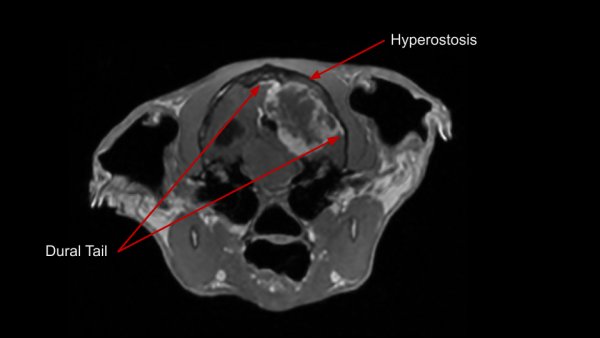

Meningiomas are typically benign and slow growing tumors arising from the meninges. They are commonly well encapsulated, focal, round, and solid. Less commonly, meningiomas can be invasive, have plaque-like shapes, or varied internal composition. They can occur anywhere along the CNS, but are most common around the brain. Meningiomas have a few key identifying characteristics; some or all may be present:

- 'Dural Tail' sign

- Hyperostosis (bony overgrowth) of the cranium by the tumor